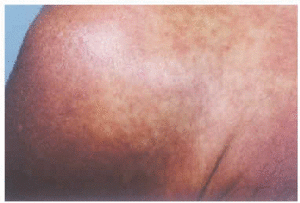

Un varón de 46 años con antecedentes personales de tabaquismo, etilismo y enfermedad pulmonar obstructiva crónica fue remitido a nuestro servicio por un oscurecimiento cutáneo progresivo a lo largo de los últimos 8 años, acompañado de prurito. También refería ocasionales cuadros de diarrea autolimitados, por los que nunca consultó a su médico. A la exploración cutánea se objetivaba una hiperpigmentación cutánea eritematopardusca casi generalizada (fig. 1). En algunas zonas, como cara y hombros, se observaban además eritema y telangiectasias (fig. 2). En abdomen y rodillas la piel aparecía engrosada, algo indurada al tacto y con remarcamiento de los surcos cutáneos. Las mucosas se encontraban respetadas. La auscultación cardiopulmonar era normal. A la palpación abdominal se detectó una hepatomegalia de 10 cm acompañada de esplenomegalia de 8 cm. No se palparon adenopatías.

Fig. 1.--Hiperpigmentación generalizada en la espalda.

Fig. 2.--Eritema y telangiectasias con mayor detalle en hombro.